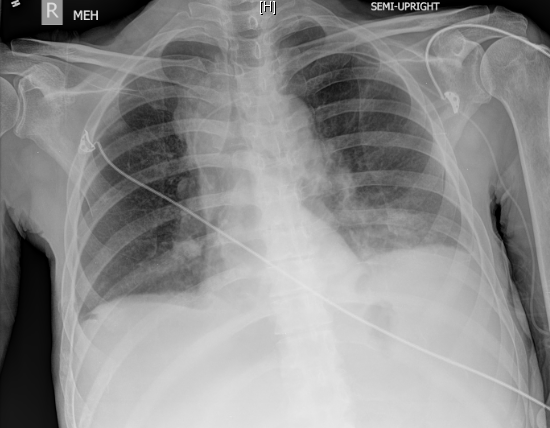

So, he didn’t have a fever in the ED, but was hypoxic and tachypneic, gradual onset of fatigue and now lethargic, volume down with an infiltrative process in his lungs. Sepsis was now the working diagnosis. Triple antibiotics coverage was ordered along with the other “usual” labs for sick patients and a prior imaging study showed that he did have mild ascites and pleural effusions from his cancer but no lung nodules/masses – putting it all together -> sepsis from pneumonia – diagnosed in 15 minutes. The chest Xray that was ordered was done about 10 minutes after…

… you see blunting of the costophrenic angles and old right rib fractures, but no true focal infiltrates – interpreted by radiology as unchanged from his prior CXR except for the rib fractures (which is interesting as it suggests a trauma occurred between the prior CXR and this one). Didn’t change the thought of the providers though, they know what they saw and knew that ultrasound is better than chest radiograph for pneumonia. He responded to fluids very well and felt markedly better within a few hours, transferred to a nasal cannula, and became more responsive with stabilization of his vitals. As an inpatient, his pneumonia on his chest XRay became more apparent the next day, he continued to improve and do well, but with a CT showing extension of his cancer.